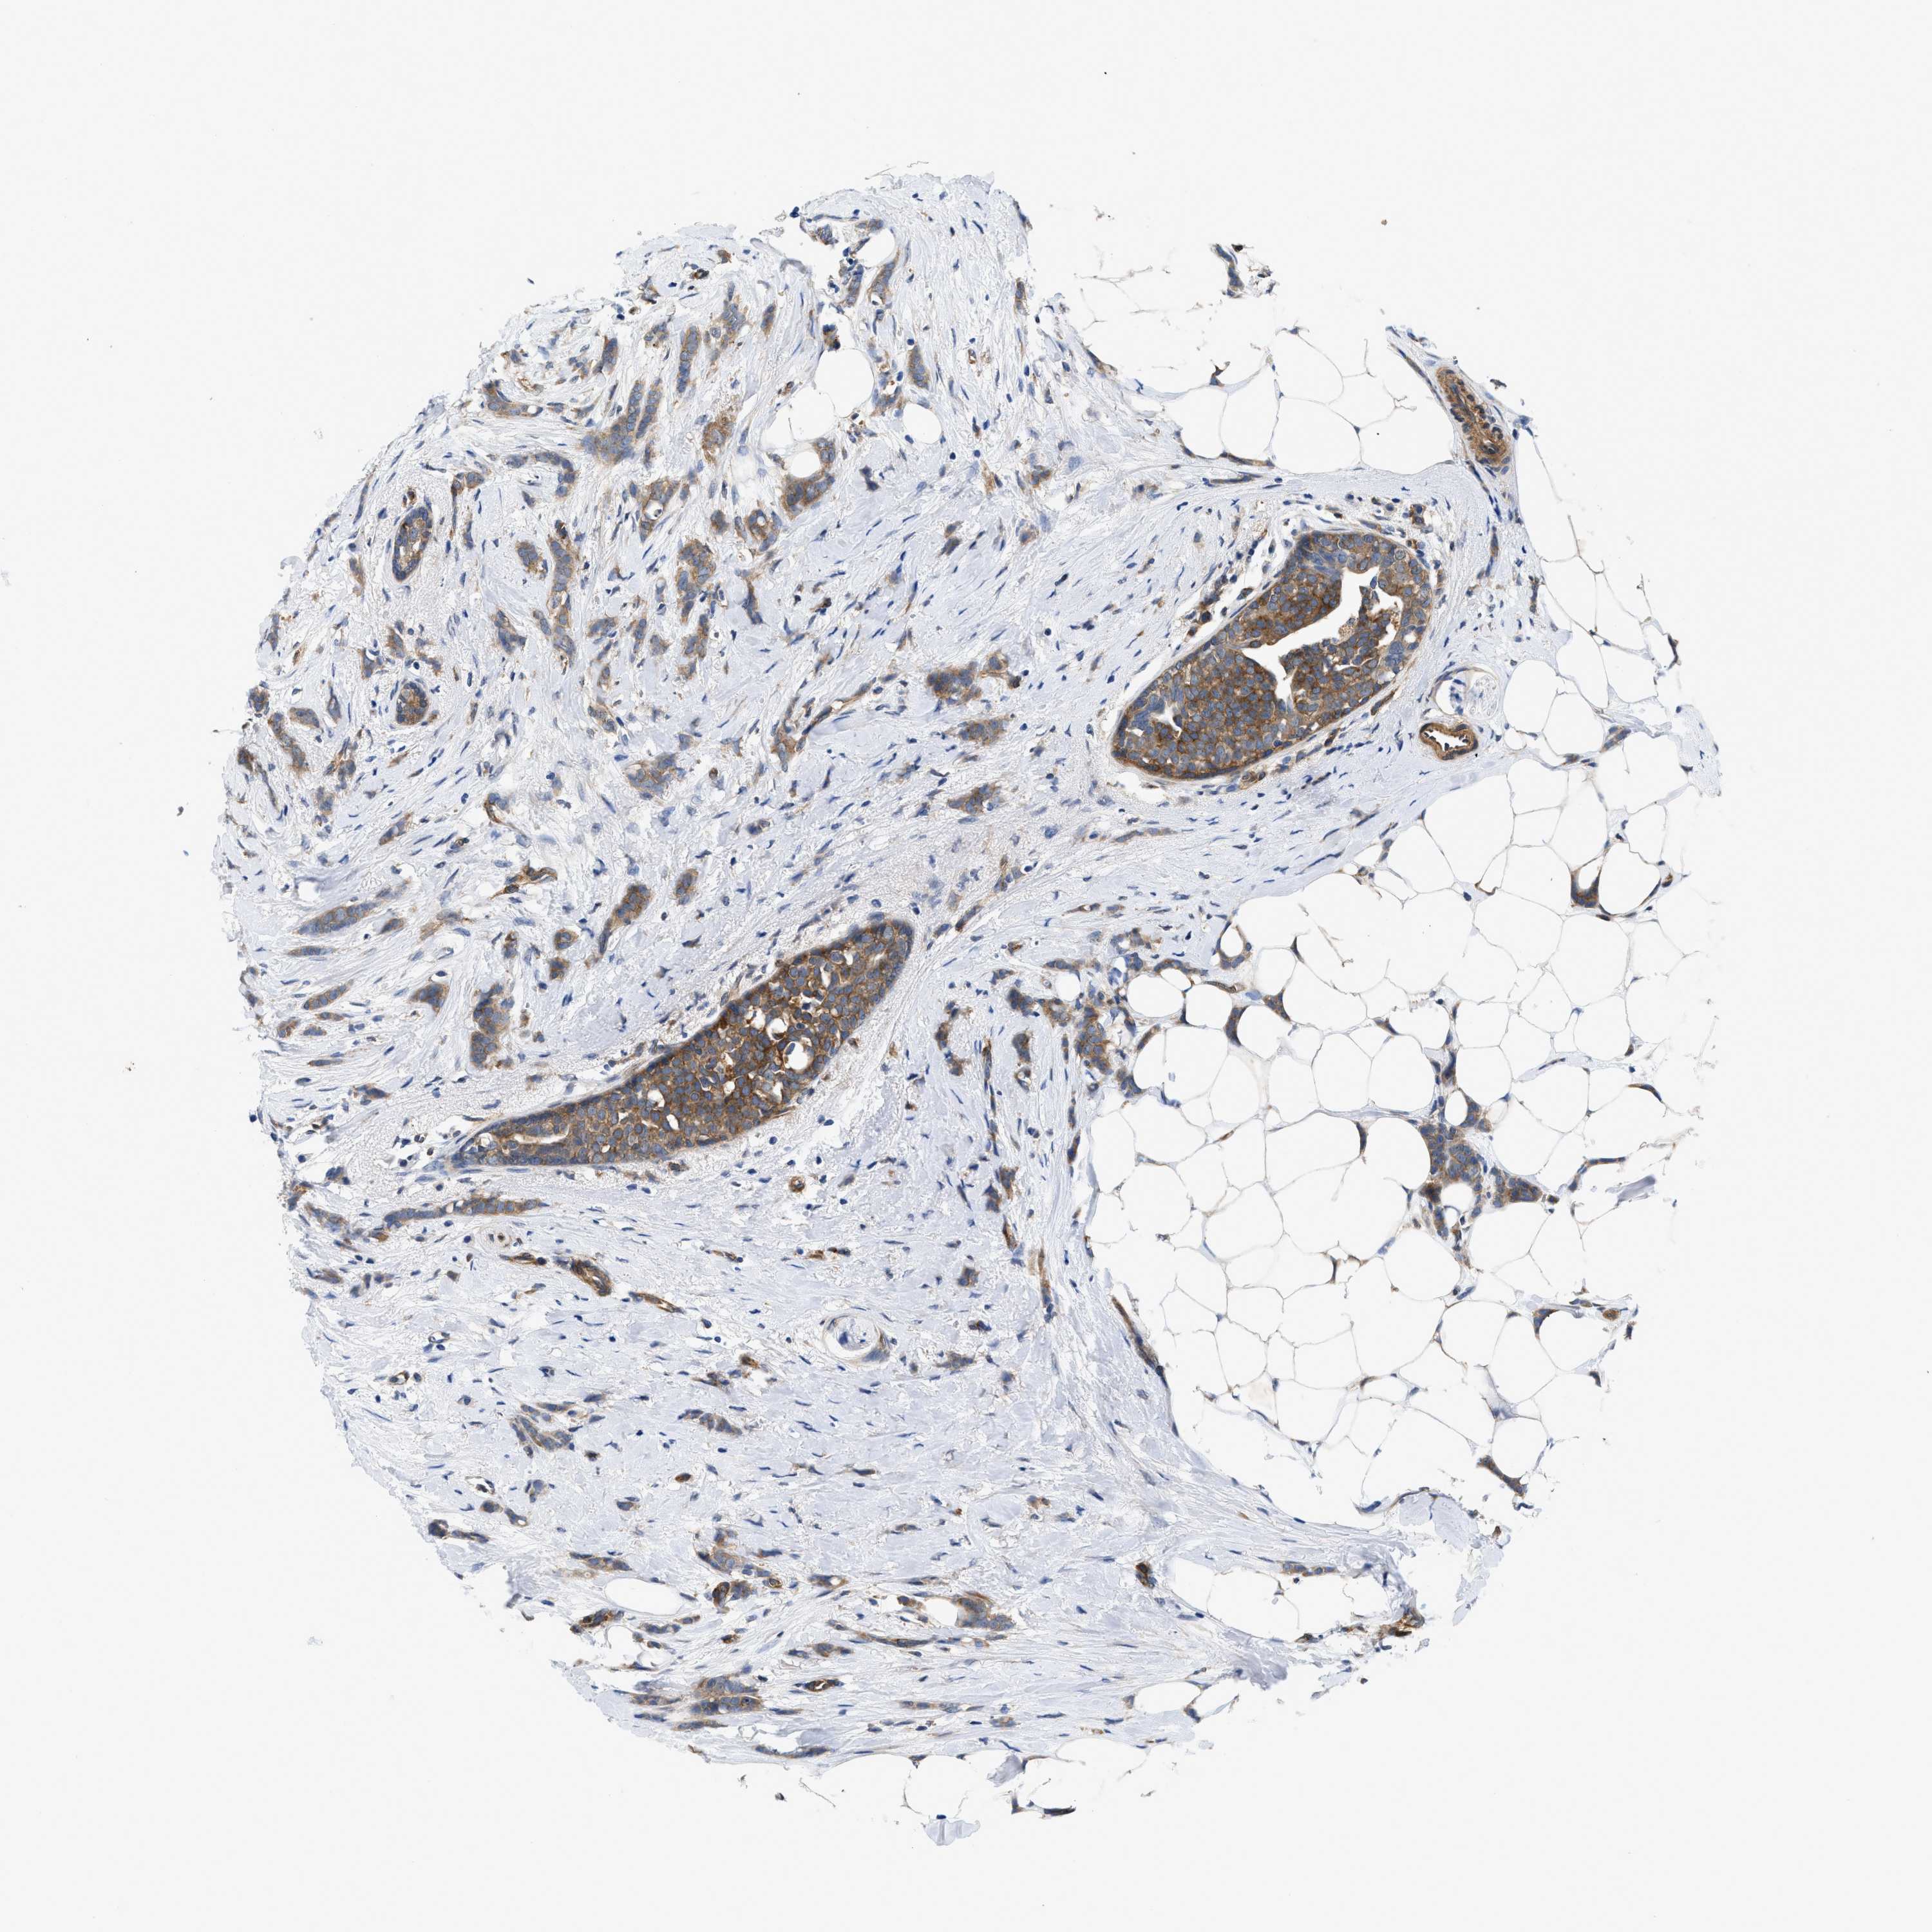

BRCA TCGA BRCA VALIDATION PROTEIN EXPRESSION

ANTIBODIES

AND

VALIDATION